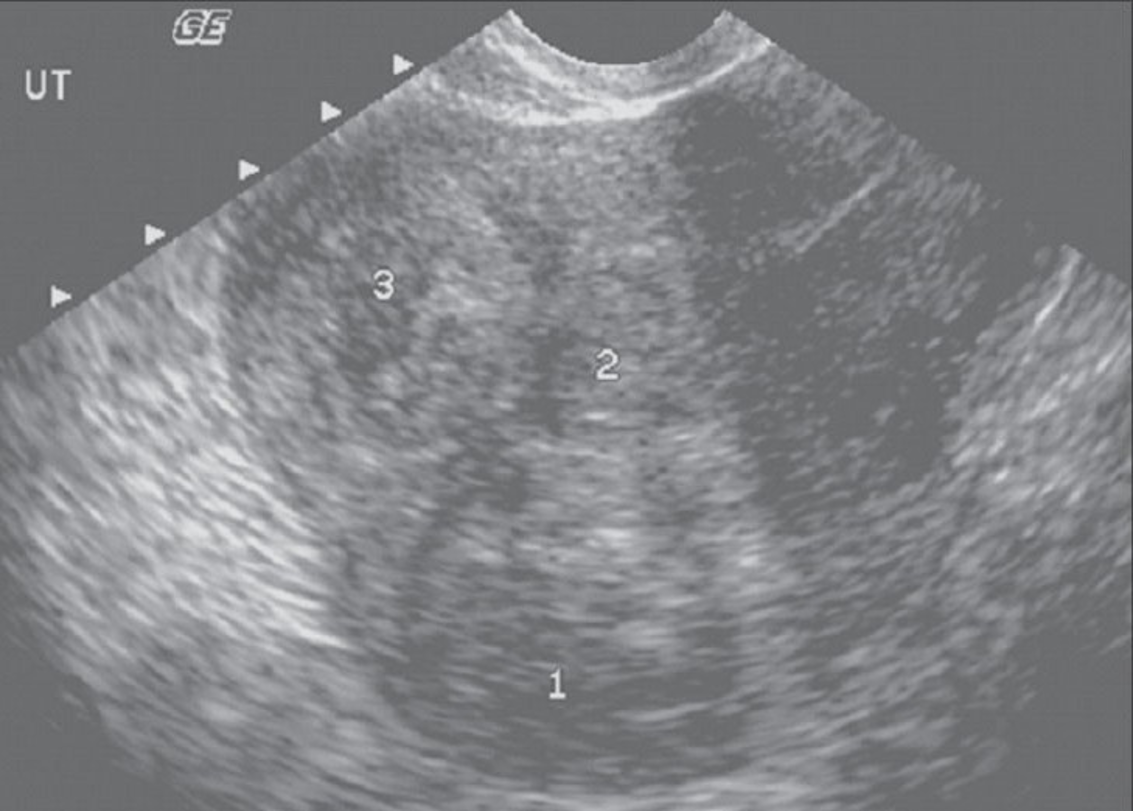

Bicornate Uterus

*